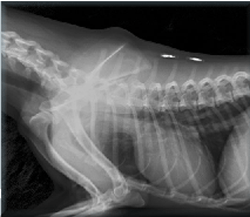

Tedavi altına alınan kedinin burada çekilen röntgeni ise şok etti. Alibaba.com 1619 röntgen kedi ürünü sunuyor. ► köpek ve kedilerde meme tümörleri tedavi ve belirtiler nelerdir? Kedi yiyen pitonun röntgen filmi.